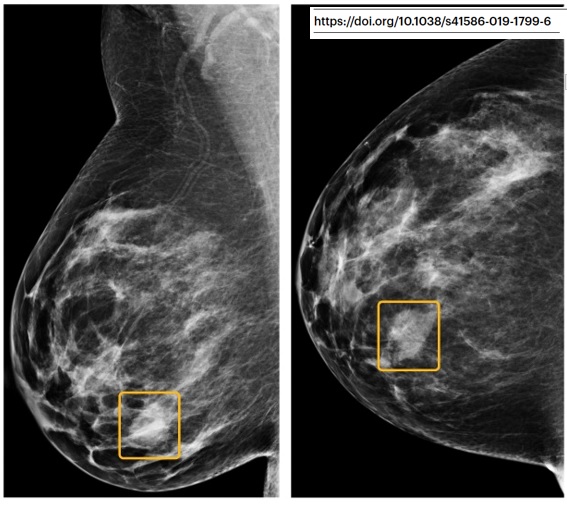

Ca veut pas dire que l’idée est naze ni que le modèle est nul, mais ça veut juste dire que la conclusion ne PEUT PAS méthodologiquement être « le modèle est meilleur que l'humain dans le soin du patient ». Exemple typique dans cet article de Google sur le cancer du sein. (17/32)

« Humain moyen », lecteurs ayant du relire des centaines d’examen rétrospectivement (= pas du tout les conditions cliniques), modèle représenté sur son set de validation interne (sa meilleure performance), etc… Bref.

Ce qui est également intéressant dans ces articles, (18/32)

c’est que la « taille de l’effet » n’est pas prise en compte dans les résultats. Par exemple, on considère de façon équivalente ce gros cancer (à gauche), vu par 6/6 radiologues mais pas par le modèle (!), et cette toute petite lésion vue par 0/6 radiologues. (19/32)

Mais dans la vraie vie ? Est-ce que la première aurait été plus agressive ? Est-ce que la deuxième aurait dû être traitée ou pas ? Ca grossit sur la mammo suivante ? Quel âge ? Quel sous-type histologique ? Bref, les patientes disparaissent au profit des images isolées. (20/32)